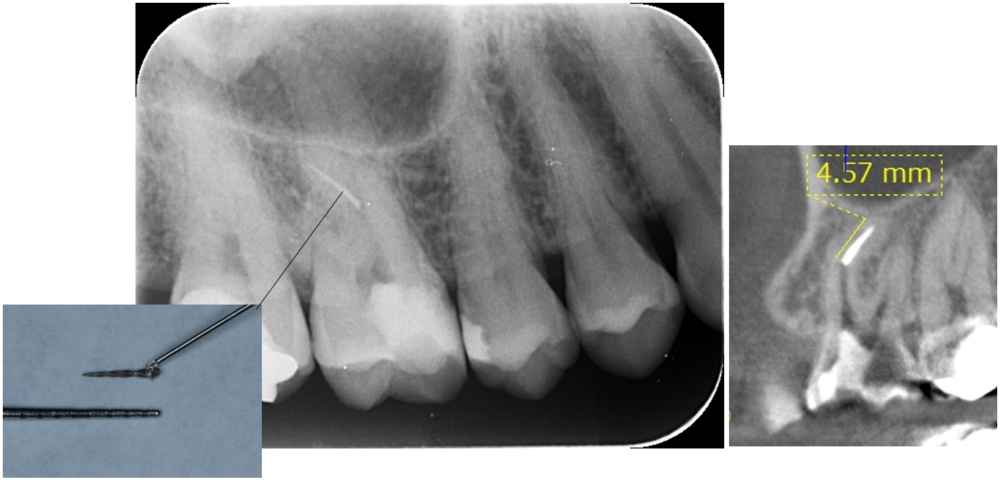

症例4

| 来院時の主訴 | 「他院で治療後、器具が歯の中で折れてしまったと言われた。治療の続きからお願いしたい。」 |

| 医院の診断 | 歯根の湾曲、人為的破折ファイルの存在 |

| 通院期間 | 1ヶ月 |

| 来院回数 | 3回 |

| 治療費 | 総額:200,000円(税抜) 【内訳】 精密感染根管治療100,000円、ファイバーポストコア20,000円、ダイレクトボンディング治療80,000円 |

4.5mm以上の破折ファイルは除去しにくいと言われています。 今回は折れてしまった破折ファイルを事前にレントゲンでチェックした所4.57mmありました。破折ファイルはループと言われる特殊な器具を用いて短時間で除去することができました。 |